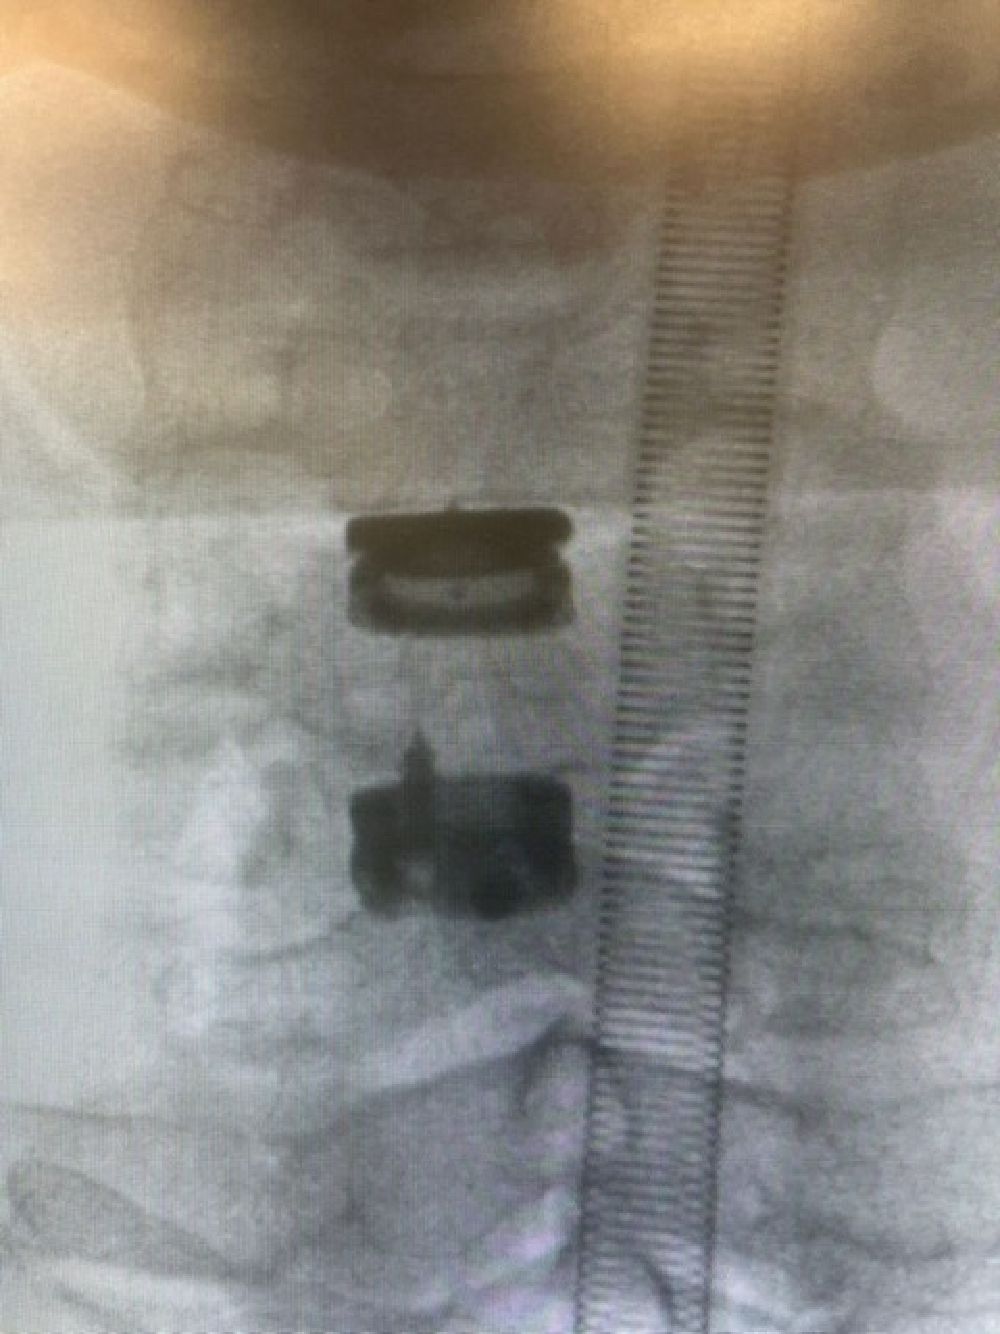

Patologia Degenerativa da Coluna Vertebral

- Tratamento de doenças que afetam a estrutura e função da coluna, com potencial impacto na qualidade de vida.

- Hérnia discal

- Fraturas osteoporóticas das vértebras